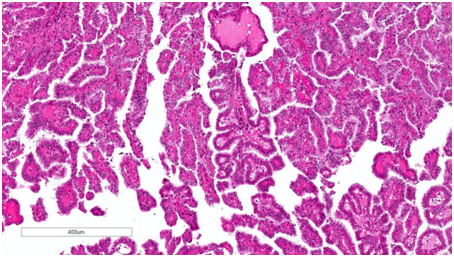

Vi thể

Kiến trúc chủ yếu là dạng nhú hoặc dạng ống–nhú. Lớp lót gồm các tế bào có hình thái đa dạng, từ các tế bào vuông nhỏ bắt màu kiềm với hạch nhân không rõ cho đến các tế bào lớn hơn,bào tương eosin với hạch nhân nổi bật; có thể gặp bào tương sáng, đây là một bẫy chẩn đoán đã biết trong ung thư biểu mô tế bào thận dạng nhú. Các tế bào có thể sắp xếp theo kiểu hàng thẳng hoặc giả tầng. Tính không đồng nhất và hình thái hỗn hợp rất thường gặp, chiếm khoảng 47–48% các trường hợp, do đó đây là một trong những lý do khiến việc phân typ không còn được ưu tiên. Thường thấy thâm nhiễm các đại thực bào bọt. Có thể hiện diện các thể cát vôi (psammoma bodies) và sắc tố hemosiderin. Các kiểu hình đã được mô tả gồm: dạng PRCC hai pha (biphasic,phế nang hoặc squamoid), với hai quần thể tế bào, các ổ tế bào lớn hơn dạng squamoid, bào tương eosin, được bao quanh bởi các tế bào nhỏ hơn bắt màu amphophilic tạo thành cấu trúc phế nang; đã ghi nhận bằng chứng diễn tiến ác tính ở tối đa khoảng 15% trường hợp. Dạng PRCC kiểu Warthin, với các nhú bào tương eosin kèm thâm nhiễm lympho dày đặc, tương tự u Warthin của tuyến nước bọt;thường là các khối u độ mô học cao và có thể biểu hiện diễn tiến lâm sàng ác tính. Dạng PRCC đặc hoặc giả đặc, với kiến trúc đặc do các cấu trúc ống và nhú bị nén ép, được lót bởi các tế bào nhỏ có nhân độ thấp; được ghi nhận có diễn tiến lâm sàng tương đối lành tính. Các kiểu kiến trúc mô học liên quan đến tiên lượng xấu hơn bao gồm dạng đặc, dạng vi nhú, hiện tượng hobnailing và kiến trúc vi nang. Hệ thống phân độ WHO/ISUP đã được xác nhận là một yếu tố tiên lượng đối với PRCC, dựa trên mức độ nổi bật của hạch nhân để phân độ 1 đến 3, và dựa trên đa hình nhân tế bào hoặc biệt hóa dạng sarcomatoid hay rhabdoid cho độ 4.

Hình 8. pRCC đặc trưng bởi cấu trúc chủ yếu dạng nhú hoặc ống‑nhú